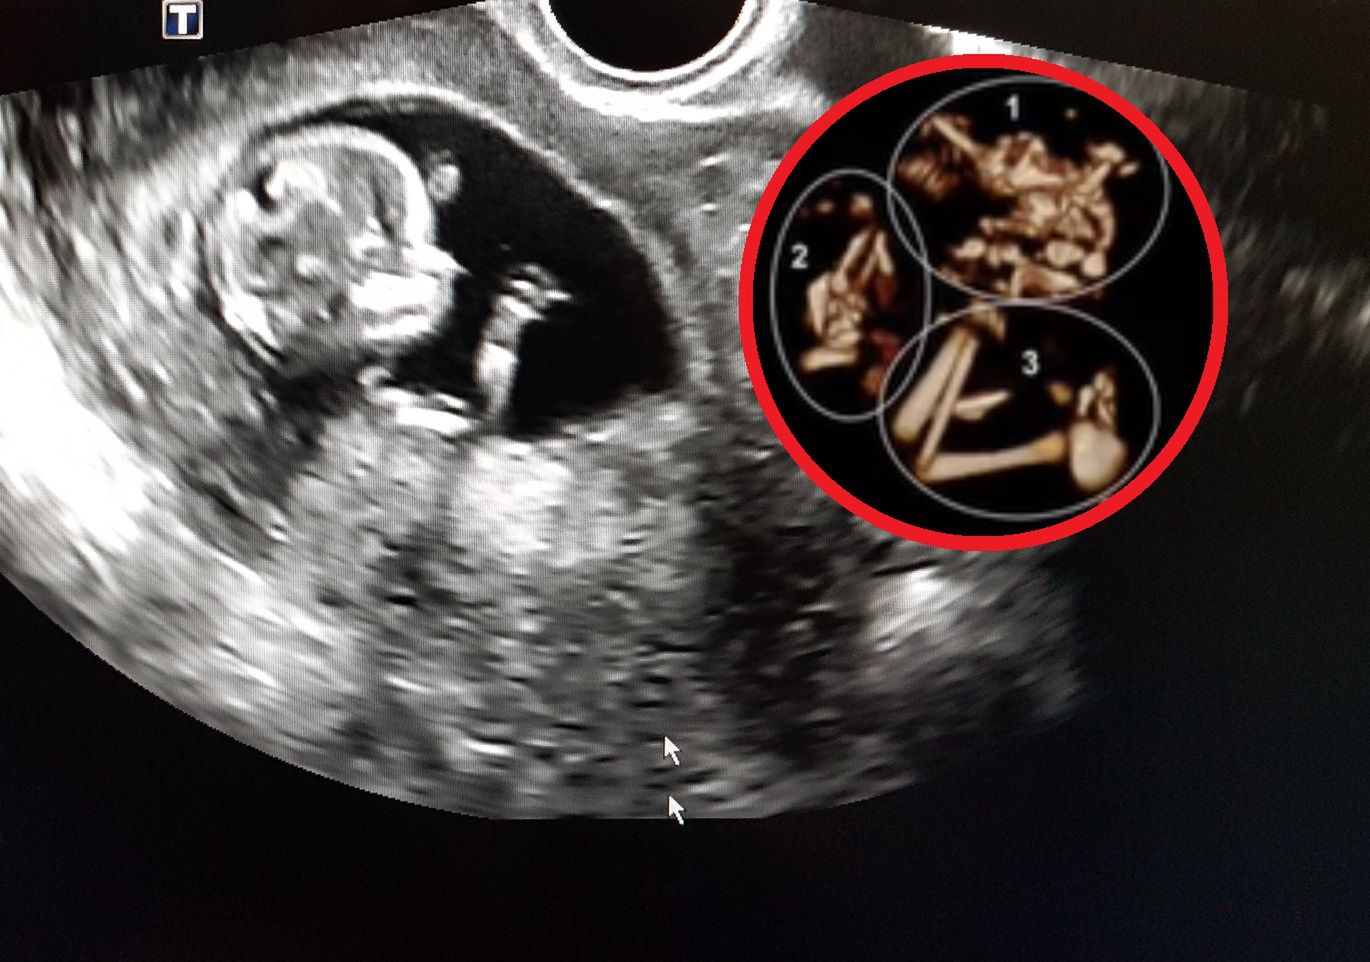

W nagraniu opublikowanym w mediach społecznościowych ekspert szczegółowo wyjaśnia, na czym polega to zjawisko i z jakim ryzykiem się wiąże. Na zdjęciu USG widać wyraźnie ślady kończyn drugiego płodu w główce dziecka. Obumarły płód podlega naturalnemu wchłonięciu przez organizm matki lub drugi płód. Komplikacje pojawiają się, gdy proces zachodzi w późniejszych etapach ciąży, wtedy może to zagrażać życiu drugiego dziecka, może dojść też do krwawienia wewnątrzmacicznego.

Neonatolog dr Michael Narvey, który opisuje całą historię, przyznaje, że to przypadki, w których trudno wybrać najlepsze rozwiązanie. Nie zawsze konieczna jest interwencja chirurgiczna. W opisywanym przypadku rodzice zdecydowali się na operację rozdzielenia płodów, mimo, że dziecko rozwijało się w miarę prawidłowo. Niestety kilka miesięcy później dziecko zmarło.